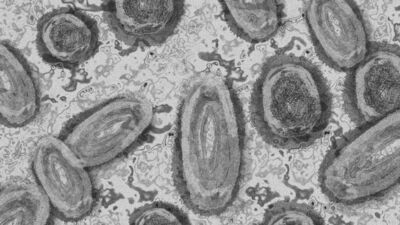

Haberler Sağlık Pakistan'da maymun çiçeği vakalarındaki artış nedeniyle 12 günlük kapanma ilan edildi | Sağlık Haberleri

Yetkililer tarafından yapılan açıklamada, kapanma, bölgede son 3 yılda tespit edilen 17 maymun çiçeği vakasının ardından bu hafta devreye alındı.

Vakaların çoğunun, salgının görüldüğü ülkelerden gelen kişilerle bağlantılı olduğu belirtildi. Bölge yönetimi, virüsün yayılımını önlemek amacıyla etkilenen alana tüm giriş ve çıkış noktalarını kapattı.